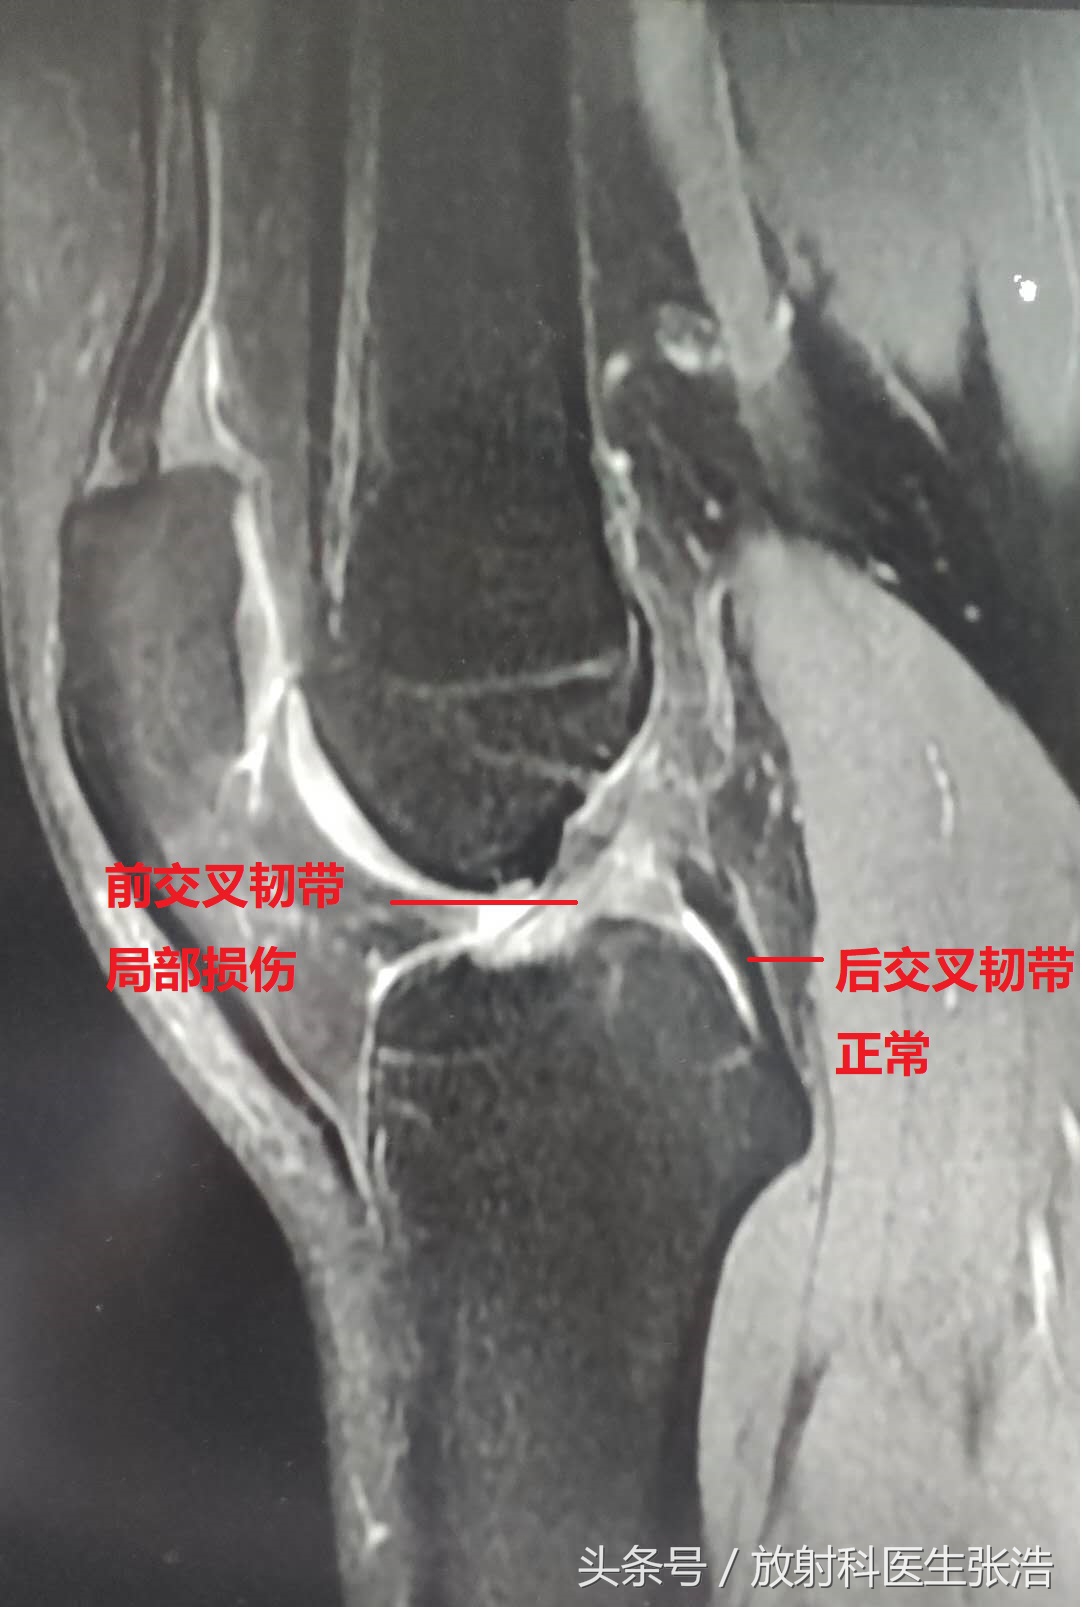

3、第三张这个问题就很严重了,往往是外伤,车祸等造成的,膝关节主要两个大韧带:前交叉韧带,后交叉韧带,一旦损伤断裂,人就没法正常行走下蹲了!可以看到后交叉韧带还是很均匀的黑色短T2信号,但是前交叉韧带信号非常不均匀,出现了局部损伤,严重的是需要及时手术治疗的!